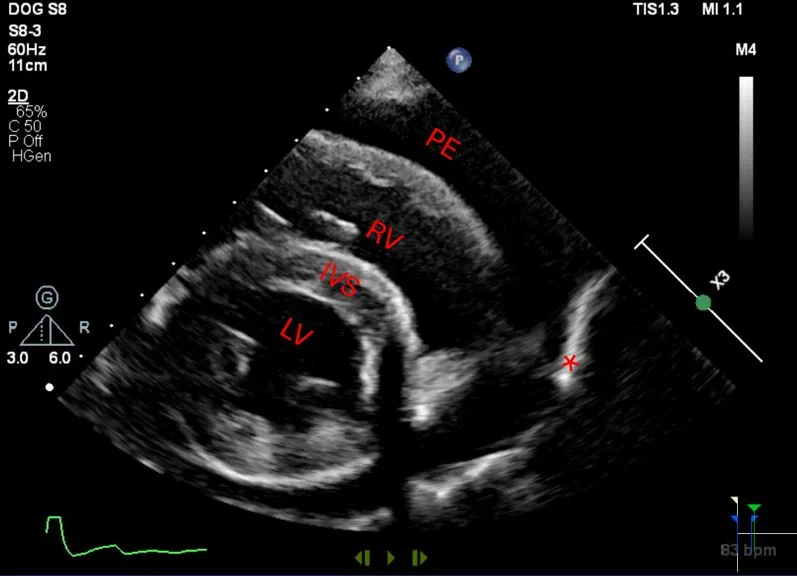

• Echocardiography confirms an echo-free space between the heart and the pericardium (Figure 1), may show cardiac tamponade (Figure 2), and may detect mass lesions.

Short-axis (hammerhead) view showing the left ventricle (LV), interventricular septum (IVS), and right ventricle (RV) surrounded by pericardial effusion (PE), which can be seen within the bright pericardium (asterisk). A short-axis view of the heart allows visualization of pericardial effusion by identifying an anechoic ring of fluid within the bright pericardium, helping differentiate the fluid from pleural effusion. Image courtesy of Meriel LeSueur, DVM

• Echocardiography